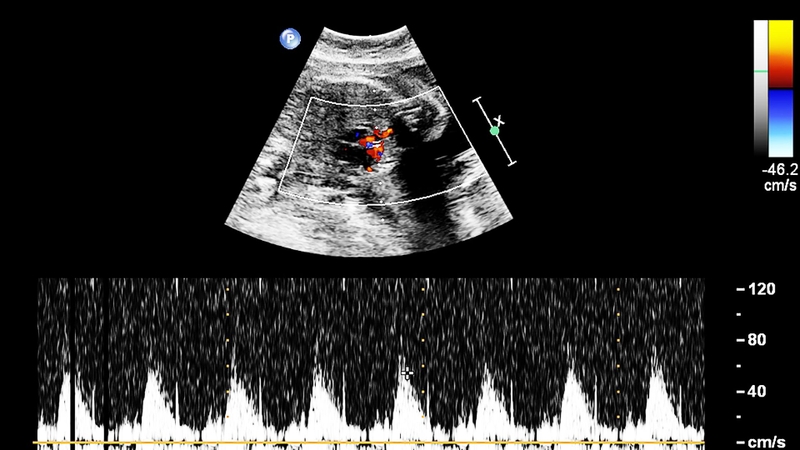

Tầm soát dị tật tim bẩm sinh là quá trình sử dụng siêu âm tim thai kết hợp với một số xét nghiệm chuyên sâu nhằm phát hiện sớm nguy cơ mắc các bất thường về cấu trúc tim ở thai nhi. Việc này giúp bác sĩ có thể lên kế hoạch theo dõi, can thiệp và điều trị phù hợp cho từng trường hợp cụ thể.

Tầm soát dị tật tim bẩm sinh là quá trình dùng siêu âm tim thai và các xét nghiệm chuyên sâu để phát hiện sớm bất thường tim ở thai nhi